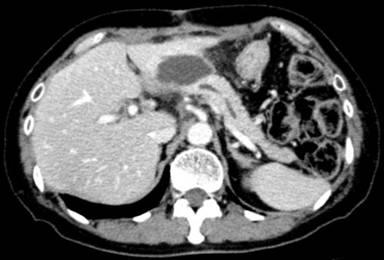

A 62-year-old woman with abdominal pain was found to have a lower biliary carcinoma. A pylorus-preserving pancreaticoduodenectomy (using the Traverso technique) with a lymph node dissection was performed. Pancreaticojejunal anastomosis was performed in an end-to-side fashion. The pancreatic duct and the jejunal mucosa were fixed. The stump of the pancreas and the jejunal wall were approximated with interrupted sutures, which were inserted through the anterior wall of the pancreas through the pancreatic parenchyma to the posterior wall. Sutures were then passed through the seromuscular layer of the jejunum, in the posterior-to-anterior direction, wide enough to cover the cut surface of the pancreas. A catheter with multiple side-holes was inserted into the pancreatic duct and sutured into place as an external stent. The stent tube was guided externally through the stump of the jejunal loop and fixed to the abdominal wall. Histological and immunohistochemical studies resulted in the diagnosis of a biliary carcinoma with lymph node metastases. The postoperative course was uneventful and the patient was discharged from the hospital 16 days postoperatively. The external stent of the pancreatic duct was removed on the 28th postoperative day. After removal, there was no output of fluid from the drain. After discharge, the patient was followed up with computed tomography (CT), ultrasonography (US), and laboratory examinations every 3 months in the outpatient ward. No notable findings were obtained (Figure 1). One year after surgery, she was admitted to our hospital for abdominal pain. All laboratory parameters, including the serum levels of tumor markers, were normal. Abdominal CT and US revealed a fluid collection around the pancreaticojejunal anastomosis (Figure 2). The size of the fluid collection was 45x33x20 mm. US-guided drainage of the fluid collection was performed. A catheter was inserted percutaneously and the fluid collection was drained. Discharge showed a gram-negative rod in the culture, and the amylase value of the discharge was significantly elevated (119,500 IU/L). Contrast radiography of the drainage tube showed no significant collection (Figure 3) and the tube was clamped. The patient was discharged from the hospital without symptoms. We evaluated the pancreatic fistula by CT and US. There was no fluid collection around the pancreaticojejunostomy.

Figure 2. Abdominal CT scan showing a fluid collection in front of the pancreaticojejunal anastomosis. |